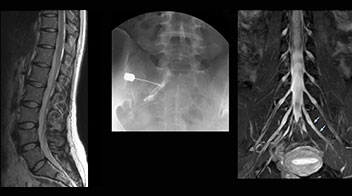

“In such case, we would then browse through axial T2-weighted MR images slice by slice and mentally reconstruct the actual situation based on both radiculography and MRI. Fortunately, NerveVIEW can now very well show nerve courses and presence of nerve compression or edema in one single image series.” “We have often seen NerveVIEW directly depict details of the nerve compression that were not observed by radiculography. Therefore, we think that with NerveVIEW we can reduce the number of invasive examinations, especially for some patients with lumbar plexus symptoms.”

“Before NerveVIEW, diagnosis by MRI alone was sometimes difficult, unless there was a strong suspicion based on clinical symptoms,” says Shoji Yabuki, MD, DMSc, Orthopedic surgeon at Fukushima Medical University School of Medicine. “This is why we routinely perform selective lumbosacral radiculography (nerve root block) and x-ray in such cases. However, radiculography can only depict nerves as far as the contrast agent reaches. When a nerve is distorted by compression, the contrast agent will not pass through this compressed area, preventing us from evaluating the full nerve compression.”